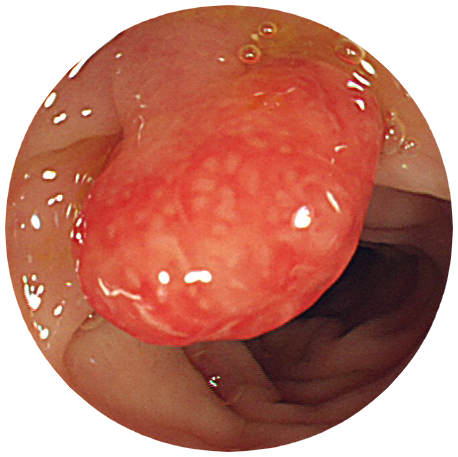

大腸疾患

UC偽ポリポーシス

説明